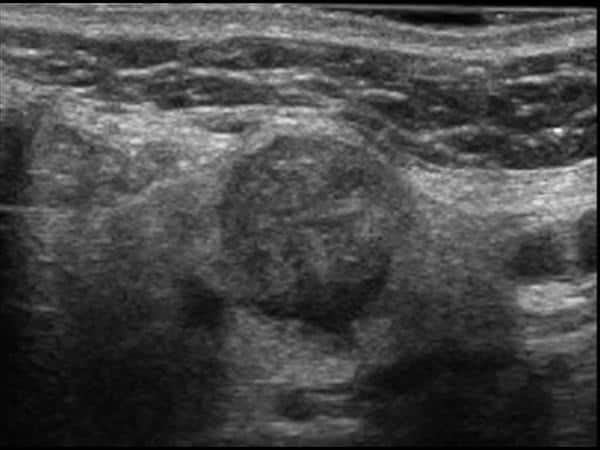

U tuyến nước bọt

» Thông tin: Nữ giới – 60 tuổi.

» Lâm sàng: Khối vùng góc hàm.

# Di căn tuyến nước bọt dưới hàm.